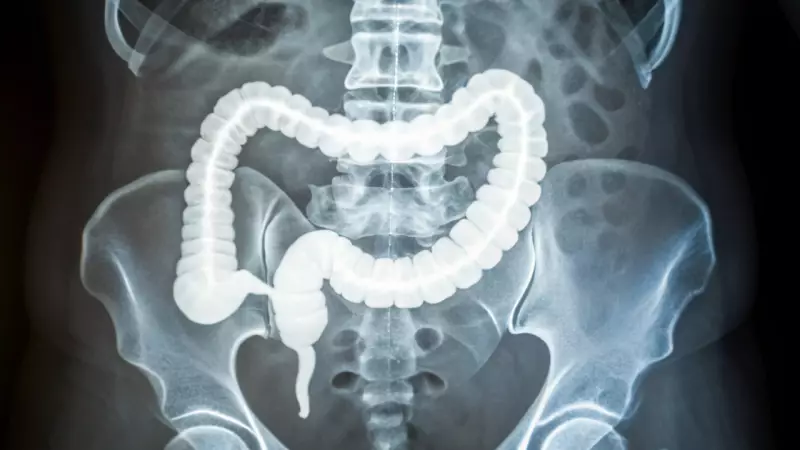

A groundbreaking new study has uncovered a critical biological clue behind the disturbing global surge in colorectal cancer cases among younger adults. Published in The Journal of Advanced Sciences, the research identifies increased stiffness in colon tissue, resulting from years of low-grade inflammation, as a potential early warning sign and accelerator for tumor growth.

For decades, colorectal cancer was primarily considered a disease of older populations, with most diagnoses occurring after the age of 50. While screening programs like colonoscopies have successfully reduced cases and deaths in that age group, a worrying reverse trend has emerged. Since 2020, early-onset colorectal cancer, defined as occurring before age 50, now accounts for roughly 12% of all U.S. diagnoses. This rate is climbing sharply, with projections indicating it could double by 2030, particularly among individuals in their 20s to 40s.

The recent study delved deep into the physical properties of colon tissue from younger patients. Researchers discovered that samples from early-onset cases were significantly more rigid than those from older patients. Upon closer examination, they found the cause: thicker, longer, and more mature strands of collagen protein, meticulously aligned. This pattern is a classic hallmark of scarring caused by repeated inflammation.